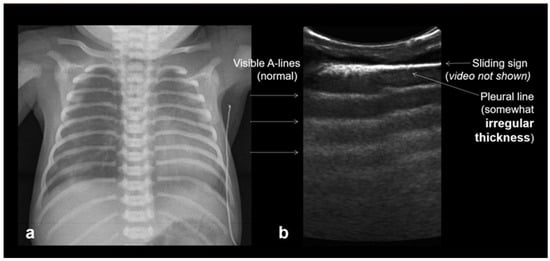

In RDS, lung ultrasound findings include consolidation or bilateral “white lung”, aero bronchograms, pleural line abnormalities, and the absence of A-lines (Figure 12, Figure 13, Figure 14 and Figure 15) [30,35,40,41].

A frequent and characteristic imaging finding in RDS is the presence of B-Lines, bilaterally and throughout the lung parenchyma, in this case bilateral B-lines with no normal parenchyma (a) (absence of A-lines). Also, note the abnormal thickening ((a,b) arrows) of the pleural line (b). The overall sense is that of white lung.

Normal to mild RDS: by chest X-ray (a); by LUS (b).